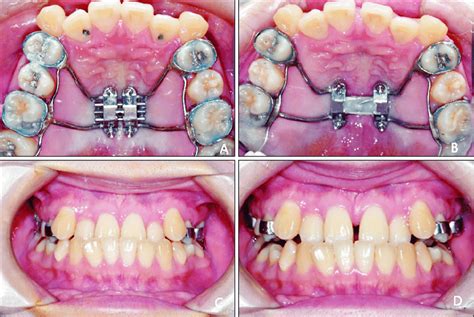

- Disyuntor de Anclaje Dentario (Hyrax): Indicado en pacientes con buen estado periodontal y dentario, paladares extremadamente estrechos y suficiente número de piezas dentarias.

No hay consenso sobre cuál tipo de disyuntor ofrece mejores resultados dentoesqueléticos y mayor estabilidad posquirúrgica. Algunos estudios no encuentran diferencias significativas entre ambos tipos, mientras que otros sugieren que los disyuntores de anclaje óseo producen mayor expansión dentaria y ósea.